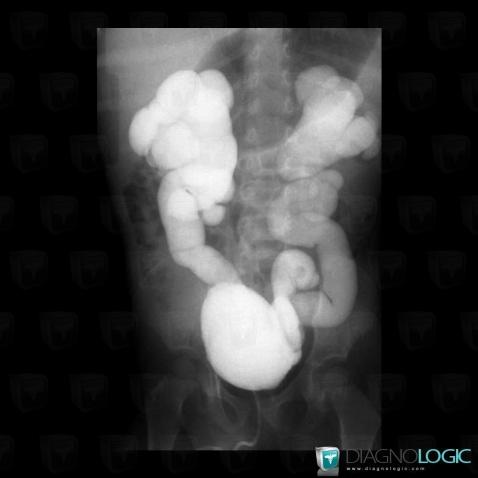

Duplicated collecting system, Ureter, X rays

Here is the specific information in the key image above:

- Diagnosis Duplicated collecting system, Location(s) Ureter, with gamuts